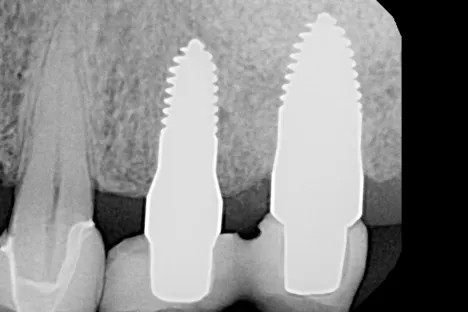

Dr.Megas_Fig.8

Fig. 8. X-ray image 7 months after implant placement.